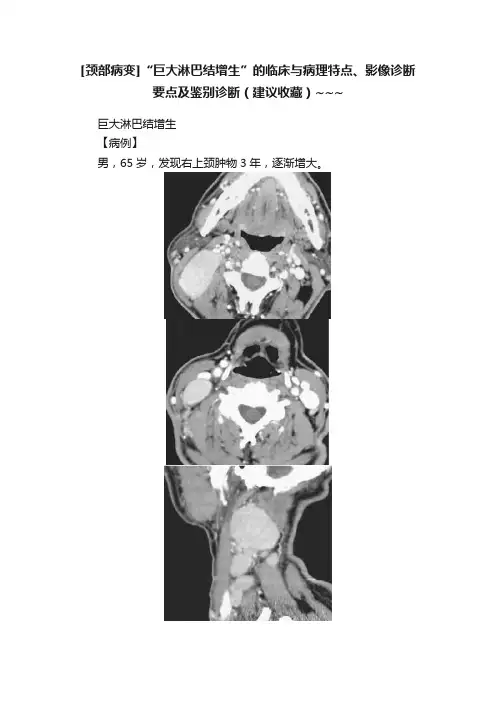

[颈部病变]“巨大淋巴结增生”的临床与病理特点、影像诊断要点及鉴别诊断(建议收藏)~~~巨大淋巴结增生【病例】男,65岁,发现右上颈肿物3年,逐渐增大。

图1【影像所见】图1A横断位CT增强扫描显示右侧颈动脉间隙肿大淋巴结,边界清楚,密度均匀,呈明显强化。

图1B 1A下方层面横断位CT增强扫描显示另一强化淋巴结。

图1C矢状位重建显示多发肿大淋巴结均匀强化,与肌肉分界清楚。

图1D冠状位重建显示右侧颈动脉间隙内见多发肿大淋巴结,边界清楚,呈显著均匀性强化。